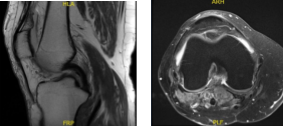

MRI results showed moderate popliteal cyst. Mild lateral patellar subluxation. Medial meniscus tear, new compared to the August 2016 MR study. Chondromalacia as detailed below. Subchondral marrow signal changes associated with patellar chondromalacia have resolved since the previous study.

MRI - 3T Right Knee Non-Contrast

MRI – 3T Right Knee Non-Contrast